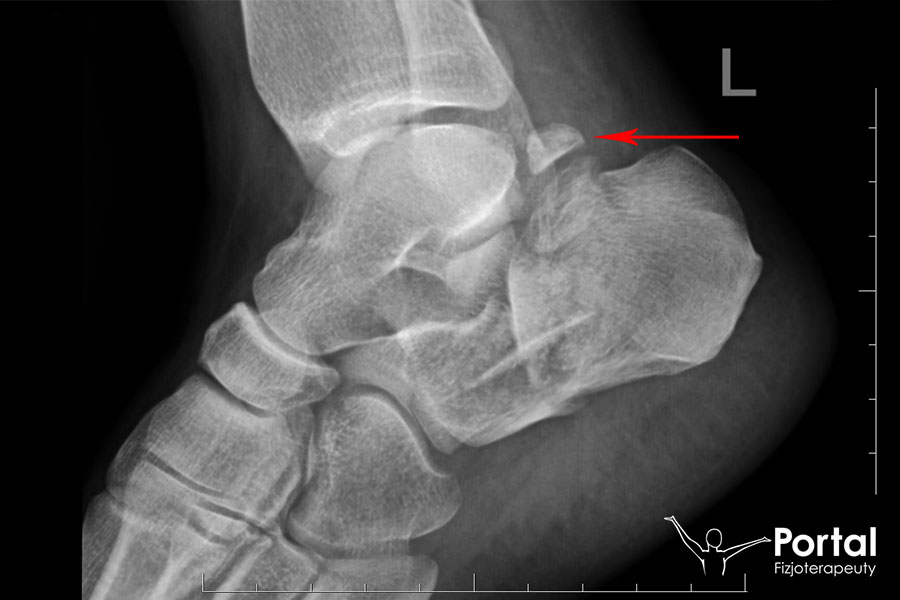

Zrost opóźniony to rodzaj zaburzeń zrostu kości, polegający na zbyt późnym kostnieniu tkanki kostnej i opóźnionym tworzeniu się stabilnego połączenia